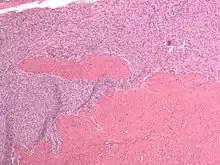

| Micrograph of a low-grade endometrial stromal sarcoma. H&E stain. | |

Low-grade endometrial stromal sarcoma consists of cells resembling normal proliferative phase endometrium, but with infiltration or vascular invasion. These behave less[3] aggressively, sometimes metastasizing, with cancer stage the best predictor of survival. The cells express estrogen/progesterone-receptors.

Microscopy

- Monotonous ovoid cells to spindly cells with minimal cytoplasm.

- Prominent arterioles. Angiolymphatic invasion common.

- Up to 10-15 mitotic figures per 10 HPF in most active areas.

- Tongue-like infiltration between muscle bundles of myometrium.

- May exhibit myxoid, epithelioid and fibrous change.

- May have foam cells or hyalinization in the stroma.